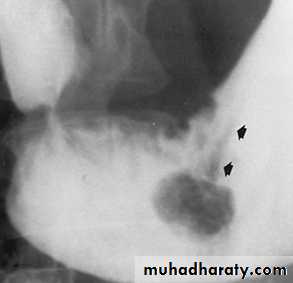

Ischemic colitis

Mucosal hemorrhage & edema cause indentations into the lumen of bowel (thumb prints)A long smooth tapered ends stricture involving the splenic flexure with sacculations